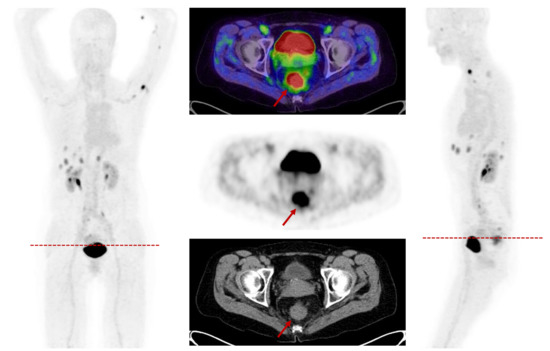

- Dendl, K.; Koerber, S.A.; Finck, R.; Mokoala, K.M.G.; Staudinger, F.; Schillings, L.; Heger, U.; Röhrich, M.; Kratochwil, C.; Sathekge, M.; et al. 68Ga-FAPI-PET/CT in patients with various gynecological malignancies. Eur. J. Nucl. Med. Mol. Imaging 2021, 1–12. [Google Scholar] [CrossRef]